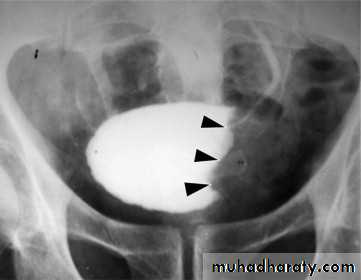

Calcification is most important feature, mainly in bladder & lower ureters , but may involve whole ureters .

In early stage inflammation may cause cobble stone appearance.

Bladder capacity not affected.

Ddgx of bladder calcification :

1. schistosomiasis .

2.tumor , TB, …